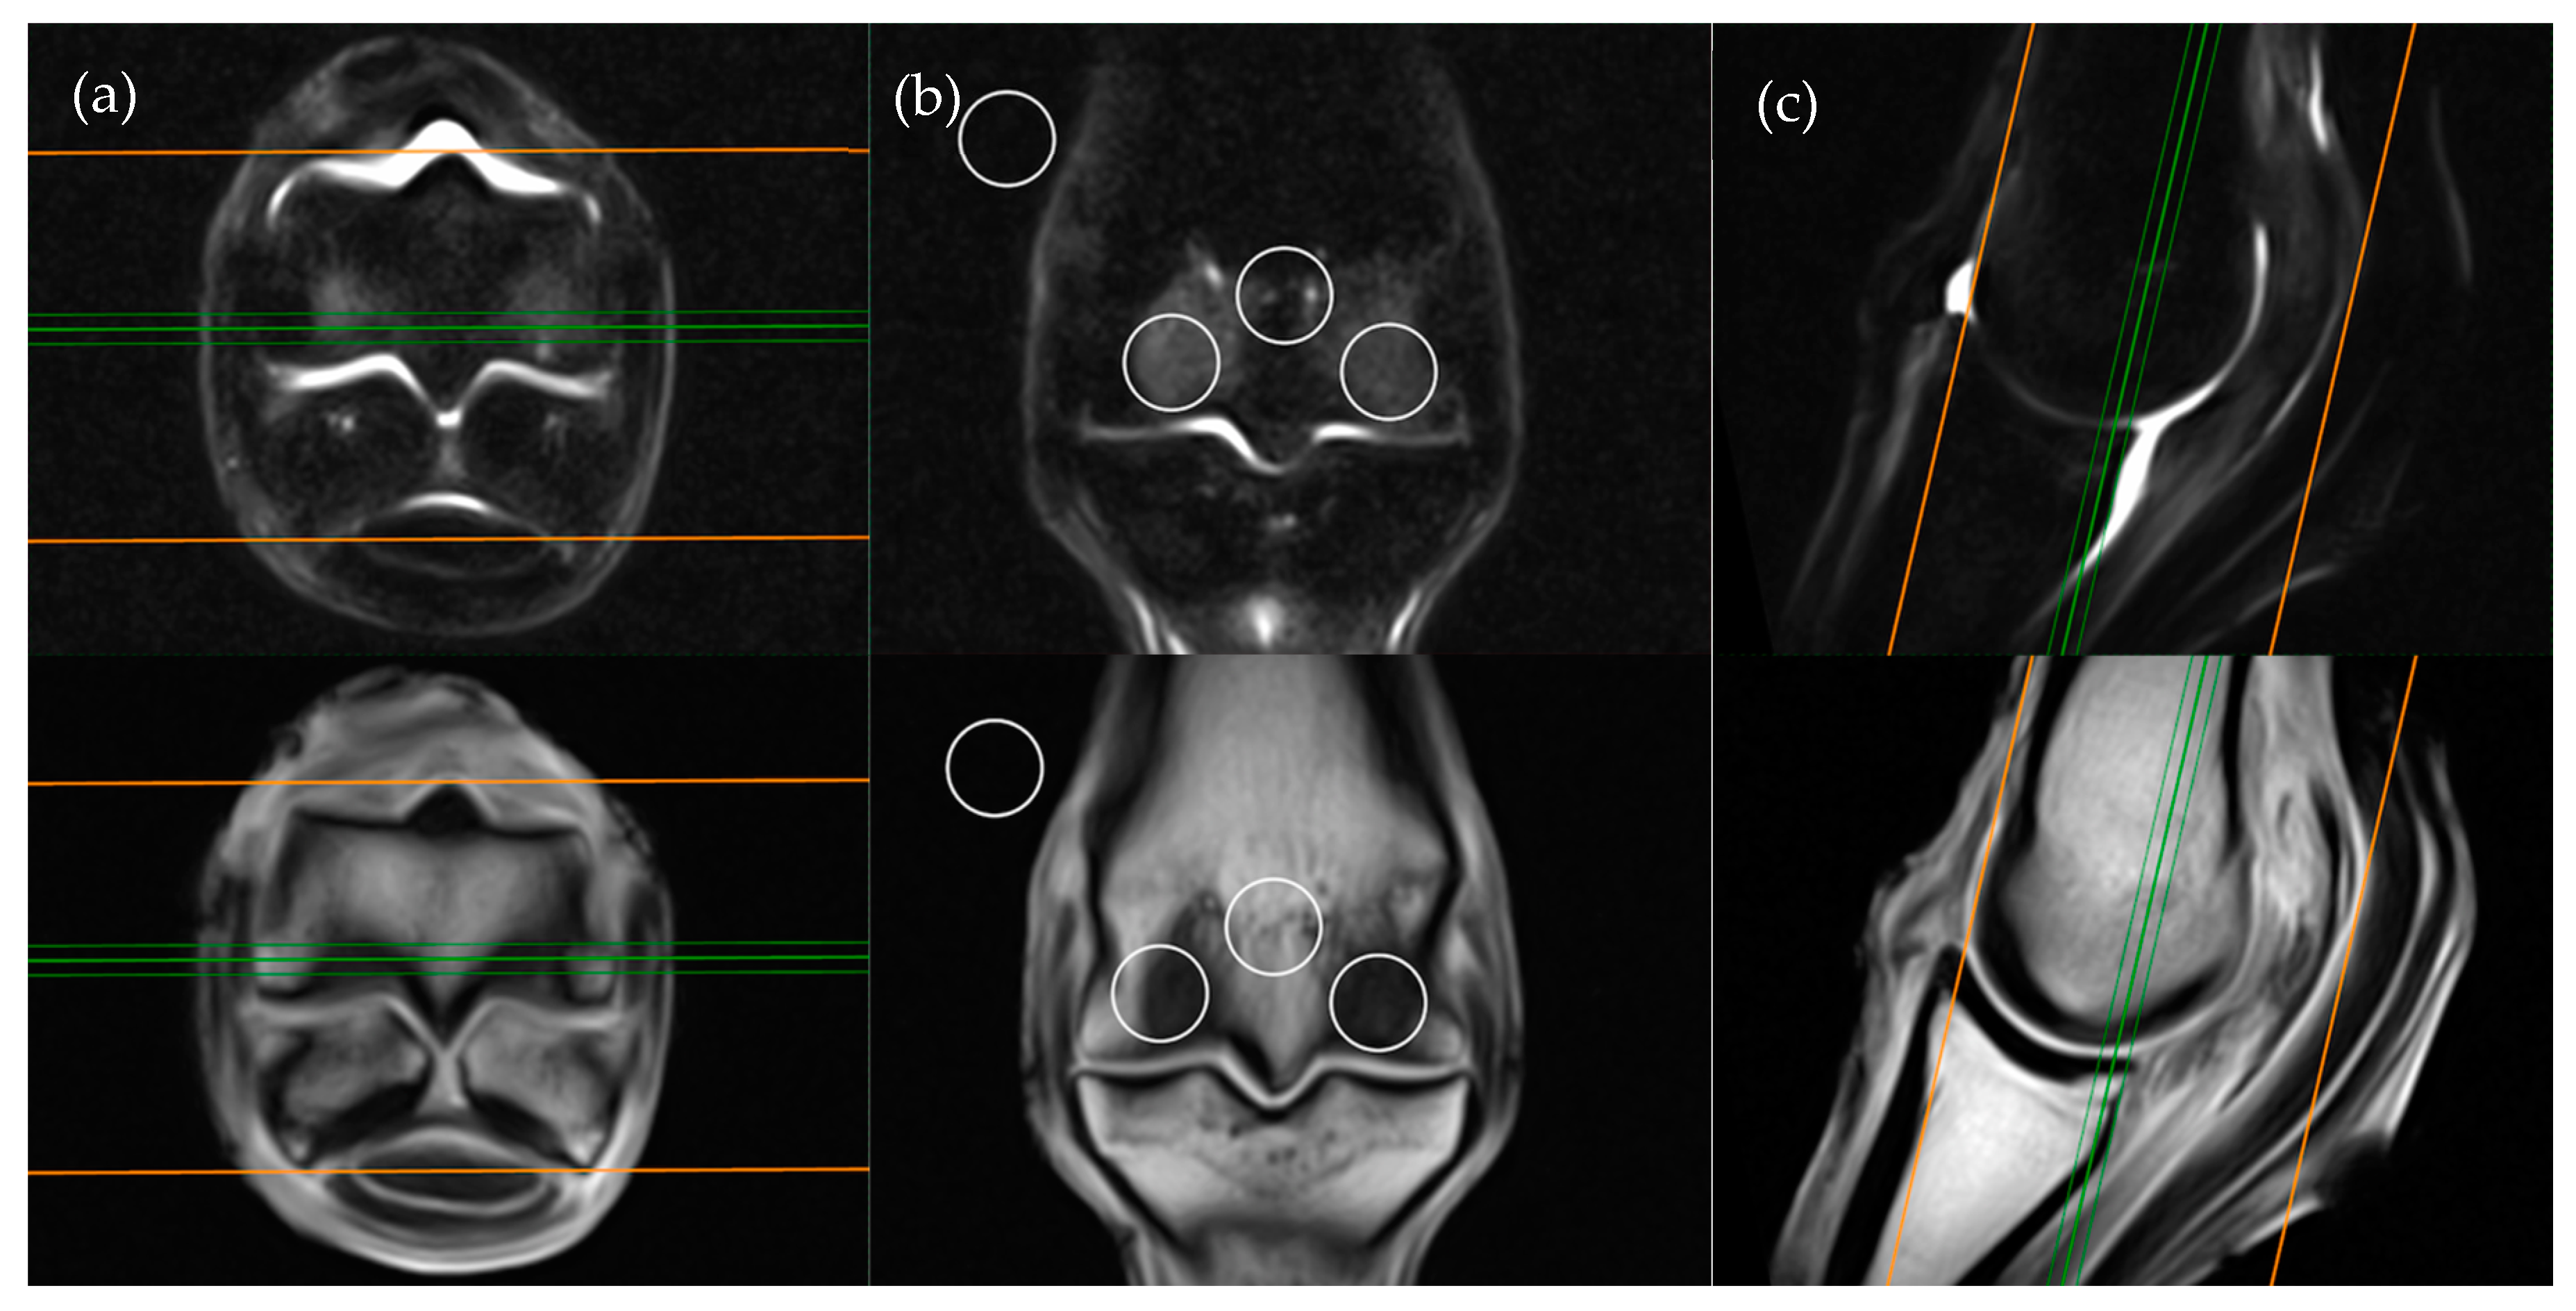

The frontal plane image slice immediately dorsal to the corticomedullary junction of the palmar/plantar cortex of the third metacarpal/metatarsal bone was used to obtain ROI measurements at the distal palmar/plantar aspect of the lateral and medial condyles as well as the axial physis (Figure 1). Condylar ROIs were placed at the edge of the subchondral bone plate within the centre of the lateral and medial condyles. The axial physeal ROI was placed on sagittal midline at the level of the physeal vasculature. The background ROI was placed at the lateral or medial surface of the limb proximal to the epicondyle of the third metacarpal/metatarsal bone.

Figure 1. Short tau inversion recovery (STIR) fast spin echo (FSE) (top row) and T1-weighted (T1W) gradient recalled echo (GRE) (bottom row) MRI images in (a) transverse; (b) frontal and (c) sagittal planes; demonstrating the location of ROI placements in a frontal plane. The green lines on the transverse and sagittal images show the standardized orientation and location of the frontal slice for regions of interest (ROI) placement. The orange lines show the extent and orientation of all the frontal slices acquired in the MRI study.